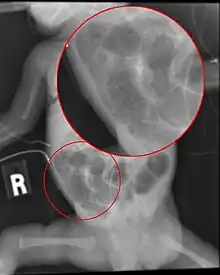

Diagnosis is usually suspected clinically, but often requires the aid of diagnostic imaging, most commonly radiography, which can show the intestines and may show areas with death tissue or a bowel perforation.[18] Specific radiographic signs of NEC are associated with specific Bell's stages of the disease:[19]

- Specific radiologic signs (pneumatosis intestinalis or portal venous gas)

- Severe radiologic signs (pneumoperitoneum)

Ultrasonography has proven to be useful, as it may detect signs and complications of NEC before they are evident on radiographs, specifically in cases that involve a paucity of bowel gas, a gasless abdomen, or a sentinel loop.[21] Diagnosis is ultimately made in 5–10% of very-low-birth-weight infants (<1,500g).[22]